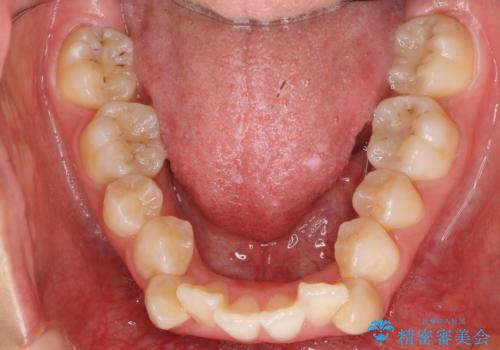

八重歯の治療 仕上がり重視で

- 八重歯を主訴に来院。

仕上がり重視とのことで、小臼歯を抜歯し、スタンダードな治療方法で仕上げています。

上下の小臼歯を抜歯しています。

矯正用インプラントアンカーを使用してしっかり前歯を下げたため、口元が大きく改善しています。